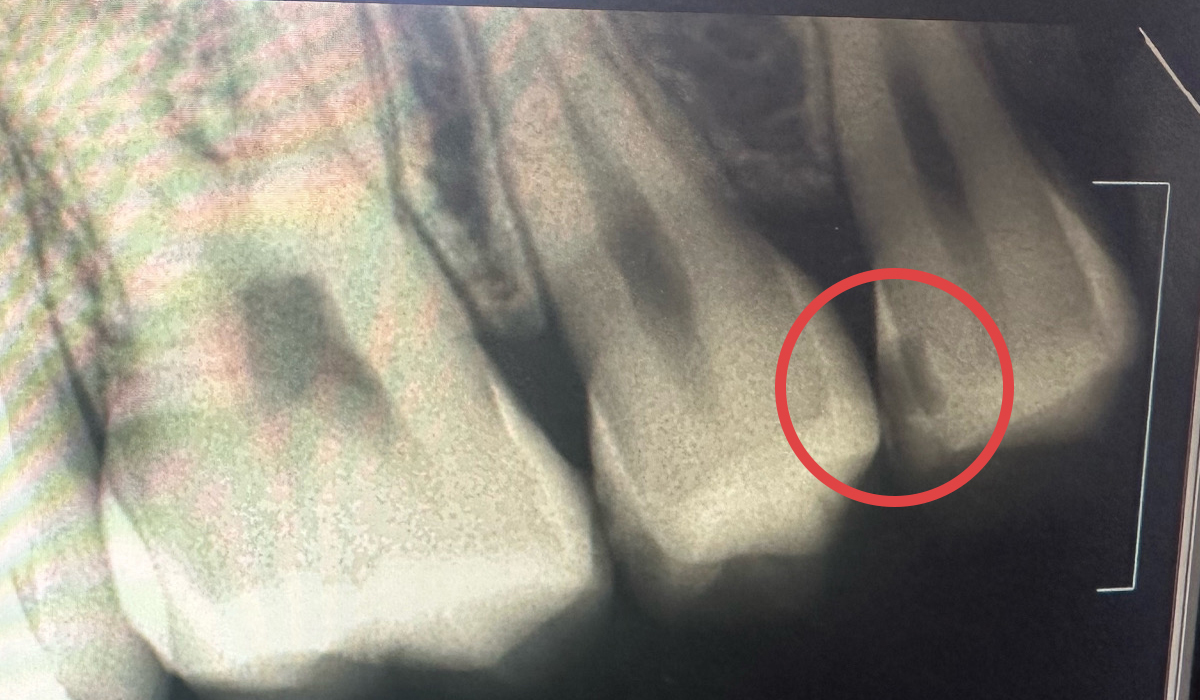

- ブラックトライアングル

ブラックトライアングル(歯と歯、歯ぐきの間にできるトライアングル状のすき間)がダイレクトボンディングで改善された症例です。